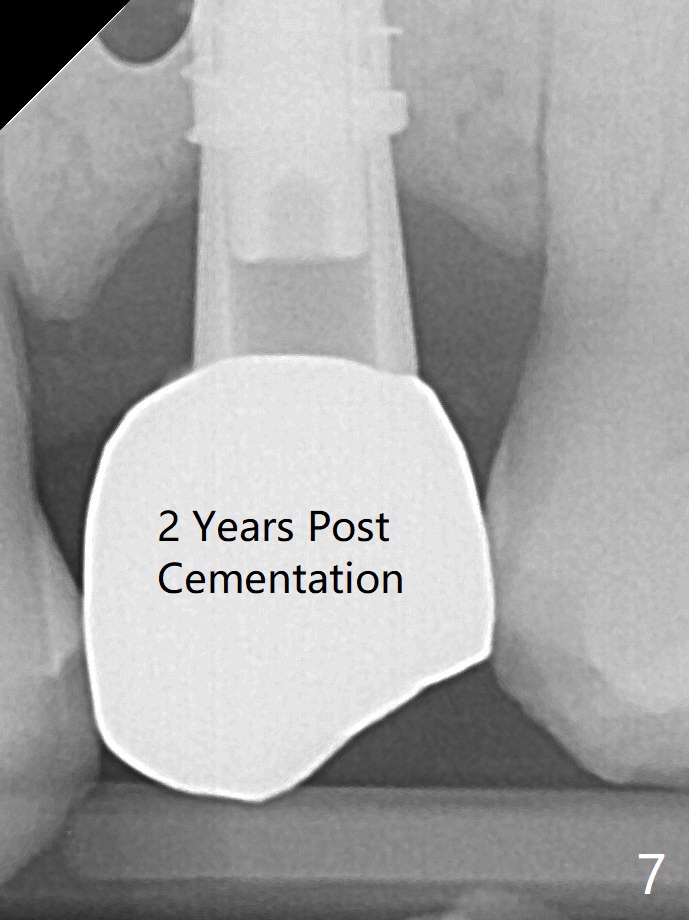

A 4x13 mm IBS implant is seated incompletely. The osteotomy is further enlarged by 3.8 mm Magic Drill for 11 mm and deepened with 3 mm drill until 18 mm. Finally the implant is placed at a satisfactory level with insertion torque > 50 Ncm (Fig.5). The patient chooses to return for impression 6 months postop (Fig.6). The abutment changes to a 4x4(4) mm one. The crown is recemented nearly 2 years post cementation, which is related to distal and deep placement of the implant and bruxism (Fig.7).